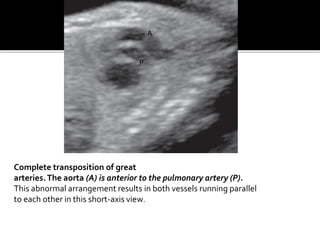

Complete transposition of great

arteries.The aorta (A) is anterior to the pulmonary artery (P).

This abnormal arrangement results in both vessels running parallel

to each other in this short-axis view.

Complete transposition ofgreat arteries.The aorta (A) is anterior to the pulmonary artery (P). This abnormal arrangement results in both vessels running parallel to each other in this short-axis view. A P